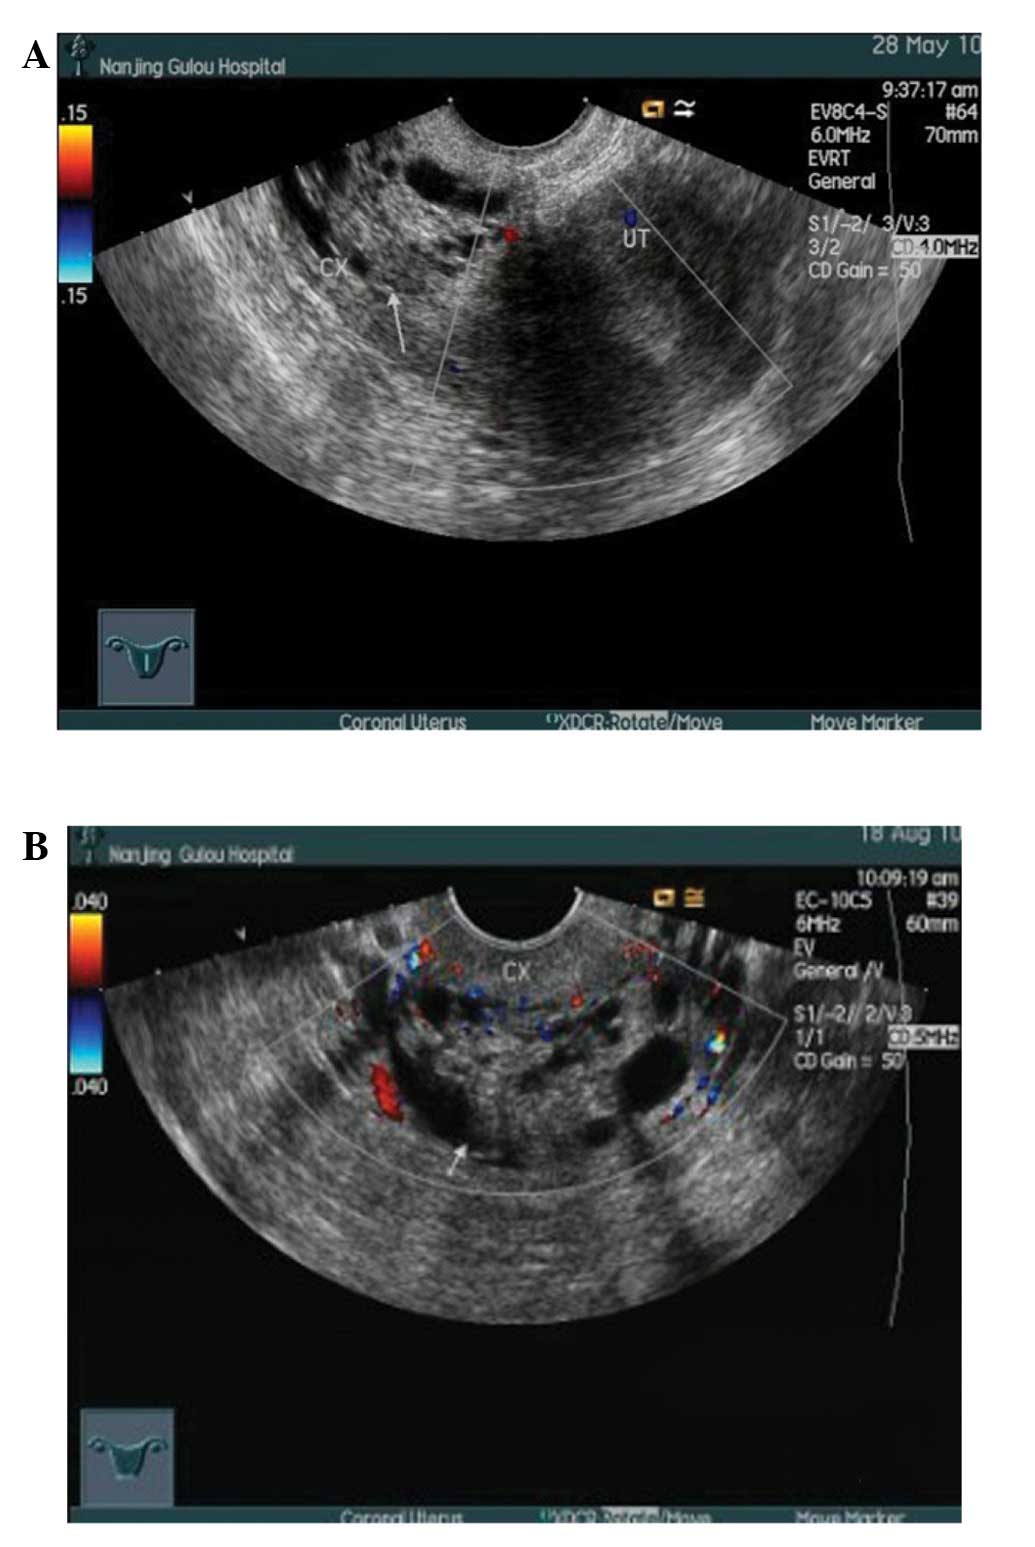

Multilocular Cystic Lesions In The Uterine Cervix: Broad ...

Subtype of cervical carcinoma that arises from the columnar epithelium of the endocervical casionally results in a cicatricial stenosis of the cervical canal. Uterine secretions, blood or infected material, frequently accumulate above the cervix. ... Retrieve Here

Echogenic Endometrial Fluid Collection In Postmenopausal ...

Attributable to cervical stenosis. He has proposed that if the endometrial tissue surrounding the fluid is thin (≤3 mm), the endometrium is inac- Postmenopausal uterine fluid collection: indicator of carcinoma. AJR Am J Roentgenol 1982; 139:529–534. 7. ... Retrieve Content